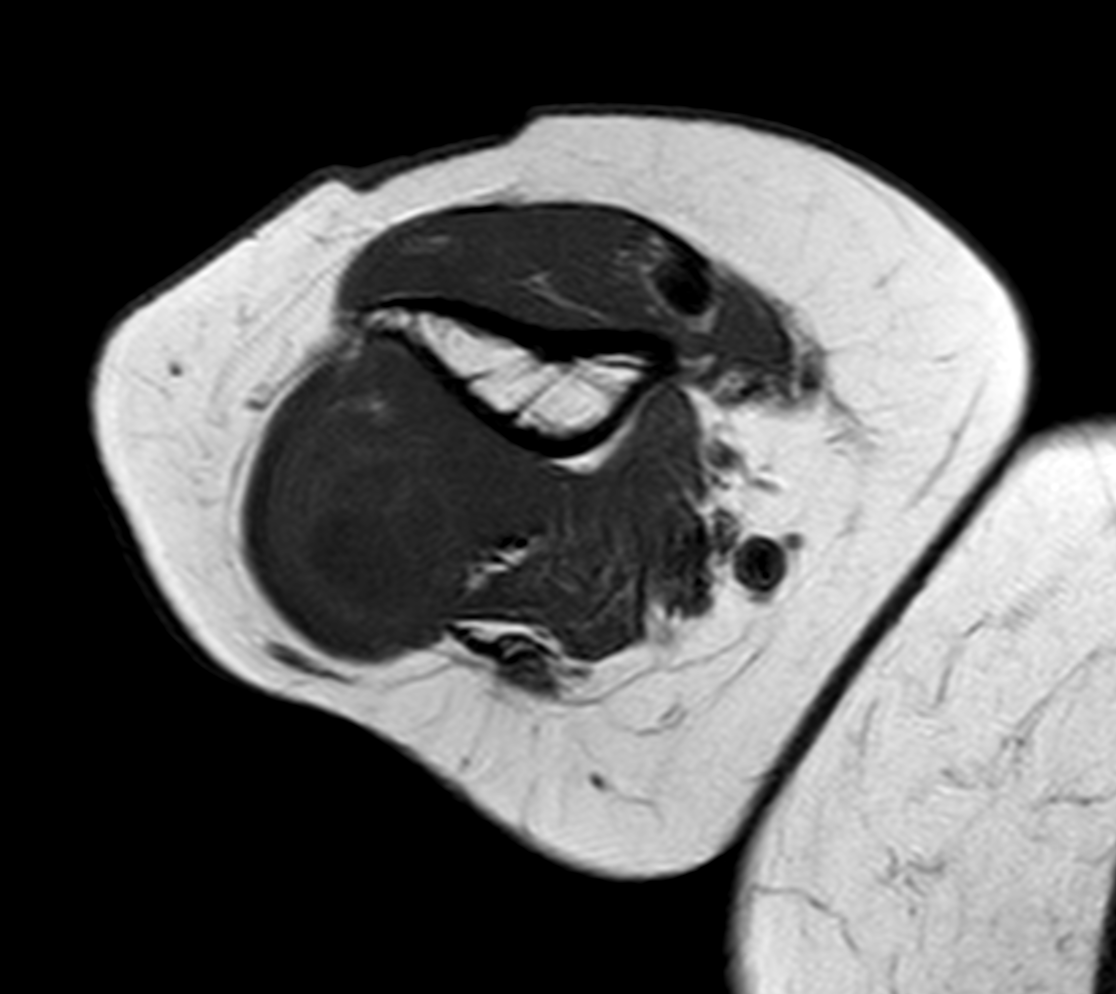

RM (T1 axial)

RM (T2 axial)